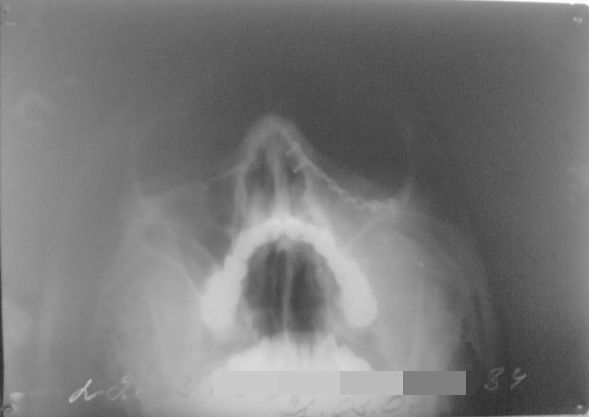

Д-з: Посттравматическая деформация средней зоны лица, последствия тяжелой ЧМТ (травма год назад), сост. после репозиции и остеосинтеза левого нижнеорбитального края мини-пластиной с винтами (08.12.06).

До операции – выраженная диплопия и западение глазного яблока, деформация нижнеорбитального края слева. После операции в течении 2-х месяцев беспокоила слезоточивость, отек век (лимфостаз), однако диплопии не было. Последние две недели слезотечения нет, лимфостаз ликвидирован (проходит курс лечения у окулиста по м/ж), однако появилась диплопия и незначительное западение глазного яблока (см. фото), выраженные меньше, чем до операции.